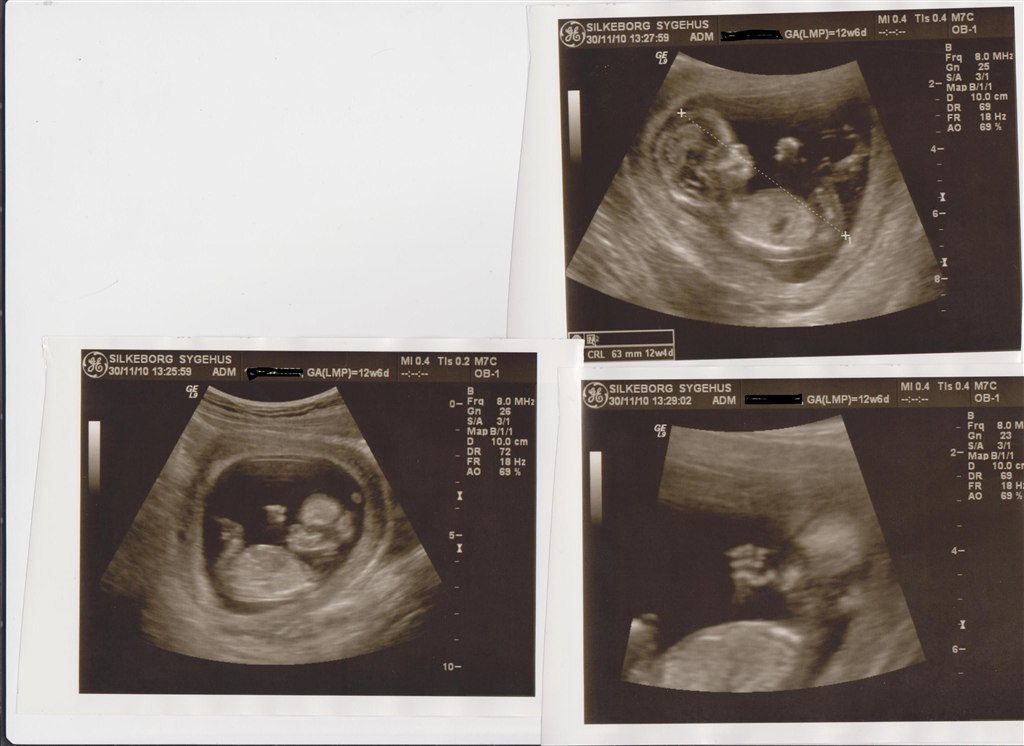

Så blev det ski min tur til at komme til NF scanning. Alt så rigtig godt ud. Chancen for mongolisme er 1 : 20322 så jeg er så glad....

Min termin bliver ikke rykket den har jeg regnet rigtig ud så ja jeg er stadig 12,6 i dag..

Den bette er 6.3cm fra hovede til numse. Og ca 12 cm fra hovede til fod.

Det er en rigtig spilopmager der er derinde. Hold da op der var gang i den inde i maven.. arme og ben boksede derud af.

Og så var vi så heldige og opleve at se den bette drak noget af fostervandet.. det så virkelig sjovt ud.

Vedhæftede fotos (klik for at se i fuld størrelse)